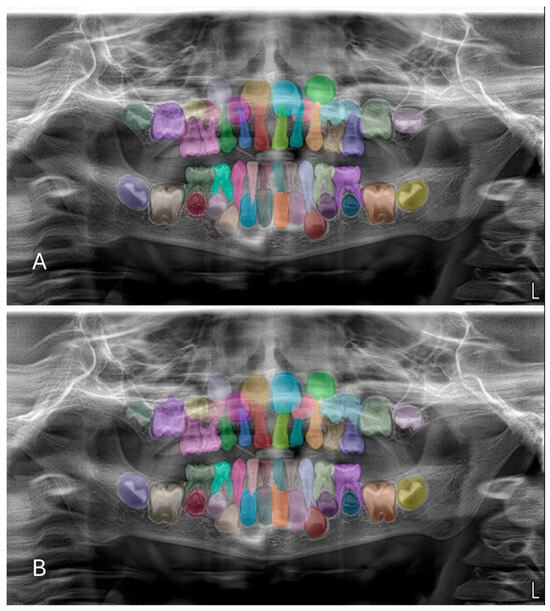

Artificial Intelligence-Based Evaluation of Permanent First Molar Extraction Indications in Children Using Panoramic Radiographs

Background: The aim of this study was to develop an artificial intelligence (AI)-based decision support model for evaluating the extraction indication of permanent first molars in pediatric patients using panoramic radiographs, and to investigate the potential contribution of this model to the clinical decision-making process. Methods: This retrospective observational study analyzed 1000 panoramic radiographs obtained from children aged 8–10 years who attended the Clinics of Batman University Faculty of Dentistry for routine dental examination. Among the radiographs meeting the inclusion criteria, a total of 176 panoramic images were selected based on dental maturation assessment using the Demirjian tooth development staging system. Cases in which the permanent second molar was classified as Demirjian stages E–F were labeled as “extraction indication present”, while the remaining stages were labeled as “extraction indication absent”. A balanced dataset was created, consisting of 88 cases in each group. Image features were extracted using Gabor filters and Histogram of Oriented Gradients (HOG). The selected features were analyzed using a Support Vector Machine (SVM) classifier with a radial basis function (RBF) kernel. Model performance was evaluated using accuracy, sensitivity, specificity, F1-score, and area under the receiver operating characteristic curve (ROC–AUC). Results: The proposed Gabor–HOG–SVM-based AI model achieved an overall classification accuracy of 77.78% with an AUC value of 0.77 in distinguishing between “extraction indication present” and “extraction indication absent” cases. For the extraction-indicated group, the sensitivity was 0.81 and the F1-score was 0.79, whereas for the non-indicated group, the sensitivity and F1-score were 0.74 and 0.77, respectively. No statistically significant differences were observed between the groups in terms of age or sex distribution (p > 0.05). Conclusions: This study demonstrates that artificial intelligence-based analysis of panoramic radiographic images can provide an objective and reproducible decision support approach for evaluating extraction indications of permanent first molars in pediatric patients. The proposed model should be considered as an adjunctive tool to reduce observer-dependent variability rather than a replacement for clinical judgment, and its clinical applicability should be further validated through multicenter and multi-parametric studies. Full article